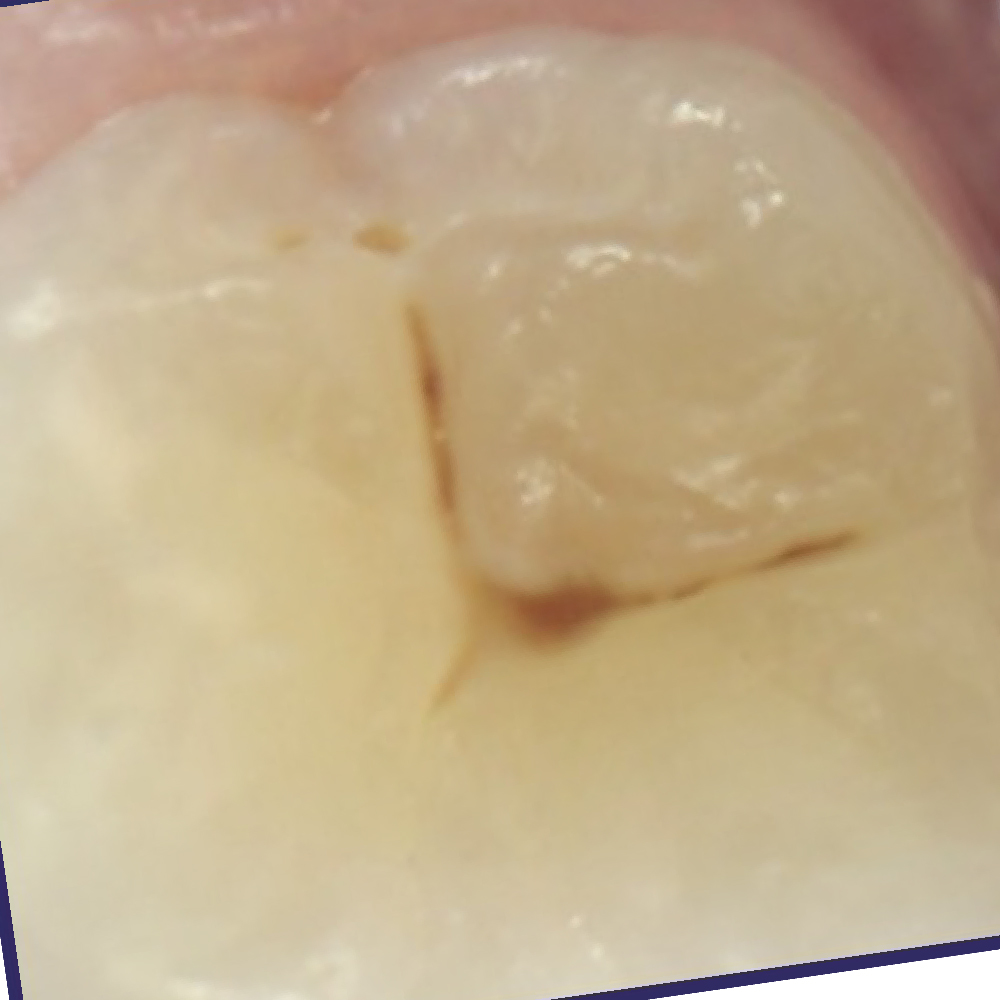

IMAGE 4

Can you differentiate?

2

EARLY

Quiz Image Overlay Overlay

Prevention/Treatment Pathway Options

High Risk or Poor Patient Compliance – Fissure Seal

Low to Medium Risk – Fissure seal or Consider Curodont or Silver Diamine Fluoride

Supported by:

• Fluoride for prevention (all teeth)

• OHI/Education

• Closely monitor the sealant or review the lesion with Calcivis

• Shorter recall

This is a classic pattern of demineralization where the established lesion has a strong bioluminescent signal accompanied by a lower signal on the mildly stained fissures.